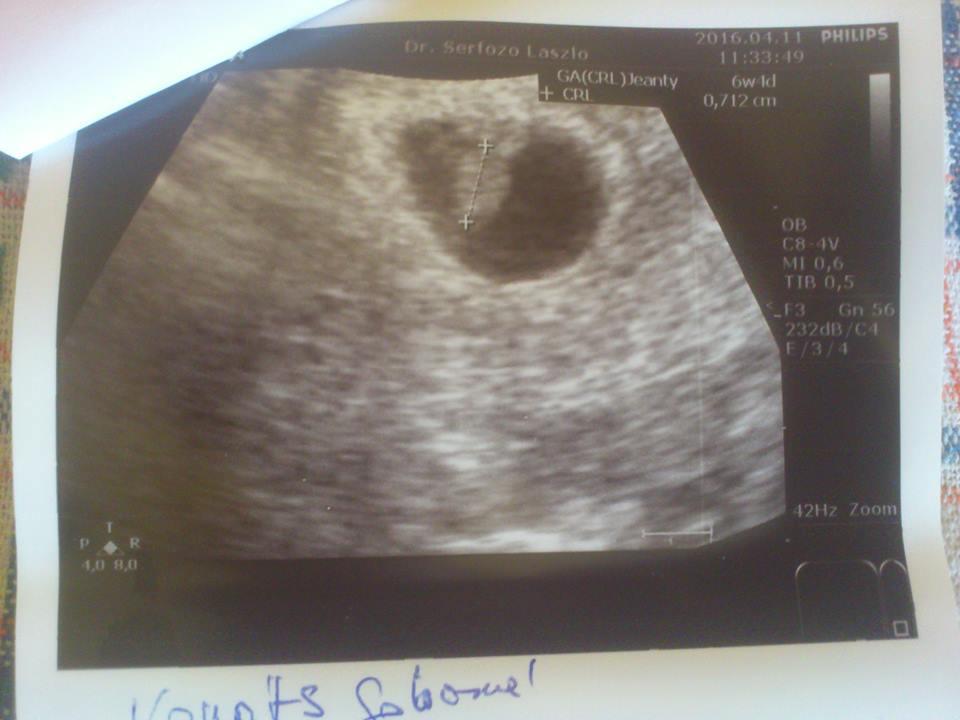

Nadehagyjuk is a múltat. MOST, ujra örölünk és reménykedünk hogy igy is marad. 6+1 vagyok utolsó menzesz alapján, de egy 2-3 nap minuszban lehetek mert pár nappal hosszabb a ciklusom 28-nál.